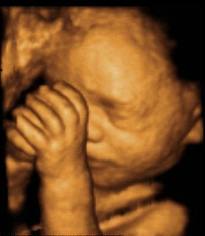

Feto cara cara2 Feto Oreja manos carita bebe Barret Barrett1 Pólipo Diverticulos Cancer rectal Transverso Duodeno Rayos%20x.jpg